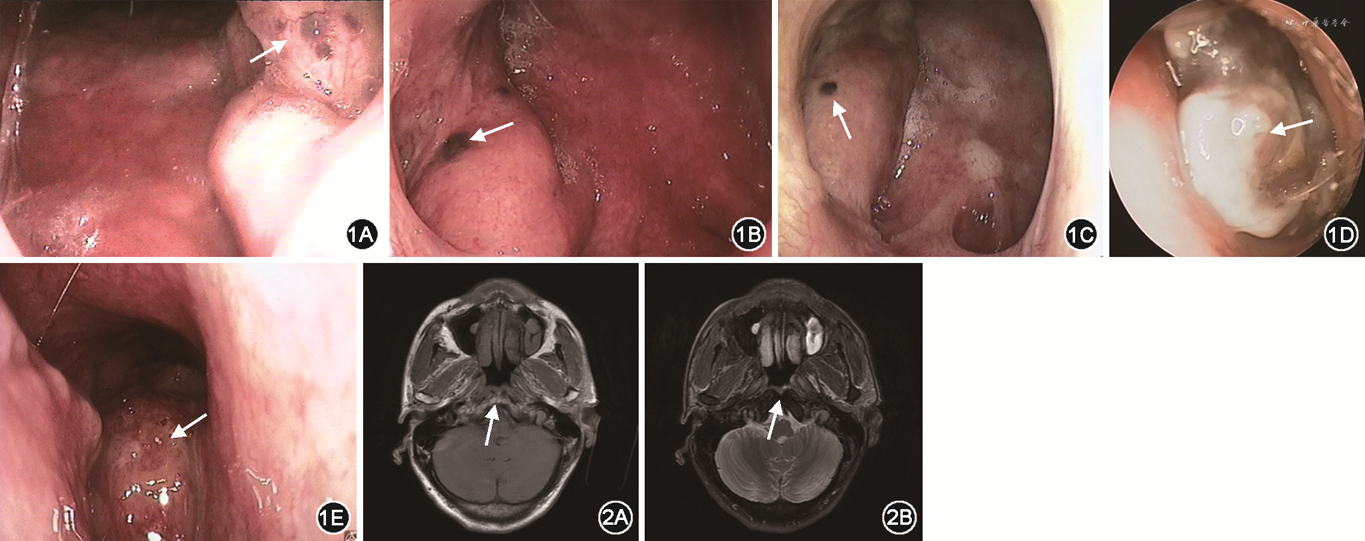

例1 患者男,52岁,因“咽喉部不适10个月”就诊于十堰市太和医院耳鼻咽喉头颈外科,伴咽喉部异物感,无明显耳鸣、听力下降等表现,门诊行电子鼻咽喉镜发现右侧咽鼓管咽口周围散在深褐色病变(图1A),遂以“鼻咽部新生物”收住入院。既往有吸烟史,平均40支/天,持续40余年。入院后行鼻咽部MR检查提示鼻咽部黏膜均匀增厚,咽隐窝及咽鼓管无明显闭塞(图2)。完善术前准备后于全身麻醉下行鼻内镜下鼻咽部病变切除术,术后组织病理学检查提示黏膜下间质内可见呈灶状分布的嗜酸性腺体,腺体内伴有色素沉着,细胞未见明显异型,病变符合黑色素性嗜酸细胞化生(melanotic oncocytic metaplasia,MOM),见图3。术后1周行电子鼻咽喉镜见手术创面恢复可,未见明显病灶残留。随访半年无复发。

例2 患者男,64岁,因“声音嘶哑2年”就诊于十堰市太和医院耳鼻咽喉头颈外科,声音嘶哑呈持续性,无明显咽喉疼痛,无咳嗽、咳痰。门诊行电子鼻咽喉镜示双侧声带肥厚,全程可见灰白色斑片状物;左侧圆枕可见新生物(图1B)。遂以“声带新生物、鼻咽新生物”收住院。既往有吸烟史,平均20支/天,持续30余年。入院完善术前准备后,于全身麻醉下行支撑喉镜下双侧声带病损切除术+鼻内镜下鼻咽病损切除术,术后组织病理学检查提示双侧声带病变符合鳞状上皮角化症;鼻咽部呈黏膜慢性炎症伴MOM。术后5 d复查电子鼻咽喉镜见鼻咽部创面恢复可,未见明显病灶残留,随访1年无复发。

例3 患者男,64岁,因“咽喉部不适10 d”就诊于十堰市太和医院耳鼻咽喉头颈外科,伴双侧鼻塞及双侧耳闷,无明显听力下降,门诊行电子鼻咽喉镜检查发现左侧圆枕有黑色突起(图1C),遂以“左侧圆枕新生物”收入院。患者既往有吸烟史,平均5支/天,持续40余年。入院完善术前准备后于全身麻醉下行鼻内镜下鼻咽病损切除术,术后组织病理学检查提示局灶性分布的腺泡呈嗜酸性化生,部分胞质内可见色素沉着,考虑为黏膜MOM。术后6 d复查电子鼻咽喉镜见鼻咽部创面恢复可,未见明显病灶残留。

鼻咽部MOM因其肉眼特征及缺乏特异性临床表现,易被误诊为痣、恶性黑色素瘤或早期鼻咽癌[19]。因不同疾病之间治疗原则不同,临床医生在诊治过程中应注意与以下疾病鉴别。(1)恶性黑色素瘤:是一种呈浸润性生长的恶性肿瘤,临床疾病进展较快,患者一般情况及预后较差。电子鼻咽喉镜下可见病变组织呈灰黑色或暗褐色(图1D),部分可伴坏死、出血。典型的恶性黑色素瘤MR表现为T1WI高信号,T2WI低信号[20, 21],显微镜下可见异型肿瘤细胞,免疫组织化学CKpan(-)。而MOM是一种较为局限的良性病变,MR无明显异常信号,宏观上可见病变组织界限清晰、表面光滑,显微镜下无明显异型细胞,免疫组织化学CKpan(+)。(2)鼻咽癌:为鼻咽黏膜的恶性肿瘤,与EB病毒感染有关,患者可有回吸涕中带血、颈部淋巴结肿大等表现。电子鼻咽喉镜下,鼻咽癌患者多以鼻咽部隆起新生物为主要表现,一般不伴有明显的色素沉着(图1E)。影像学上,鼻咽癌MR一般表现为T1WI等信号,T2WI稍高信号,增强后可有强化现象。因此,临床医生可根据其临床表现及影像学特点进行初步鉴别,但组织病理学检查是鉴别恶性肿瘤与良性病变的金标准。(3)Warthin肿瘤:嗜酸细胞上皮局灶性排列成双层细胞,这种形态学表现类似腮腺Warthin肿瘤[22]。然而,相对腮腺Warthin肿瘤而言,MOM的病变更小,在淋巴间质中缺乏纤维囊和生发中心[23],且Warthin肿瘤的淋巴细胞主要是B细胞[14]。